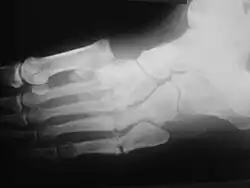

Radiologic findings

First, it is important to recognize that two types of abnormality may be detected. One is termed atrophic, in which there is osteolysis of the distal metatarsals in the forefoot. The more common form of destruction is hypertrophic joint disease, characterized by acute peri-articular fracture and joint dislocation. According to Yochum and Rowe, the "6 D's" of hypertrophy are:

The natural history of the joint destruction process has a classification scheme of its own, offered by Eichenholtz decades ago:

Stage 0: Clinically, there is joint edema, but radiographs are negative. A bone scan may be positive before a radiograph is, making it a sensitive but not very specific modality.

Stage 1: Osseous fragmentation with joint dislocation seen on radiograph ("acute Charcot").

Stage 2: Decreased local edema, with coalescence of fragments and absorption of fine bone debris.

Stage 3: No local edema, with consolidation and remodeling (albeit deformed) of fracture fragments. The foot is now stable.

Atrophic features:

- "Licked candy stick" appearance, commonly seen at the distal aspect of the metatarsals

- Diabetic osteolysis

- Bone resorption